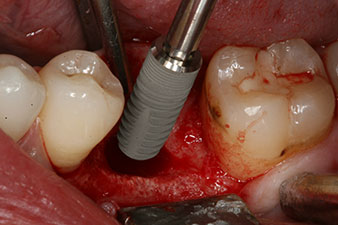

The torque used for the machine-driven placement was 43 Ncm. In addition, after screwing a measuring post (SmartPeg) specially matched to the implant, the ISQ value was measured with the probe of the W&H Osstell ISQ module.

This module is an optional extra for the W&H Implantmed and is docked to the implantology motor (see Fig. 11). The dimensionless ISQ value immediately after insertion was 64 orovestibular and 68 mesiodistal (maximum value = 100).

These values could have indicated open healing or even immediate restoration. Due to the insufficient crestal bone volume at the implant, the region was augmented with the bone chips collected during preparation of the implant bed and sutured to exclude saliva.